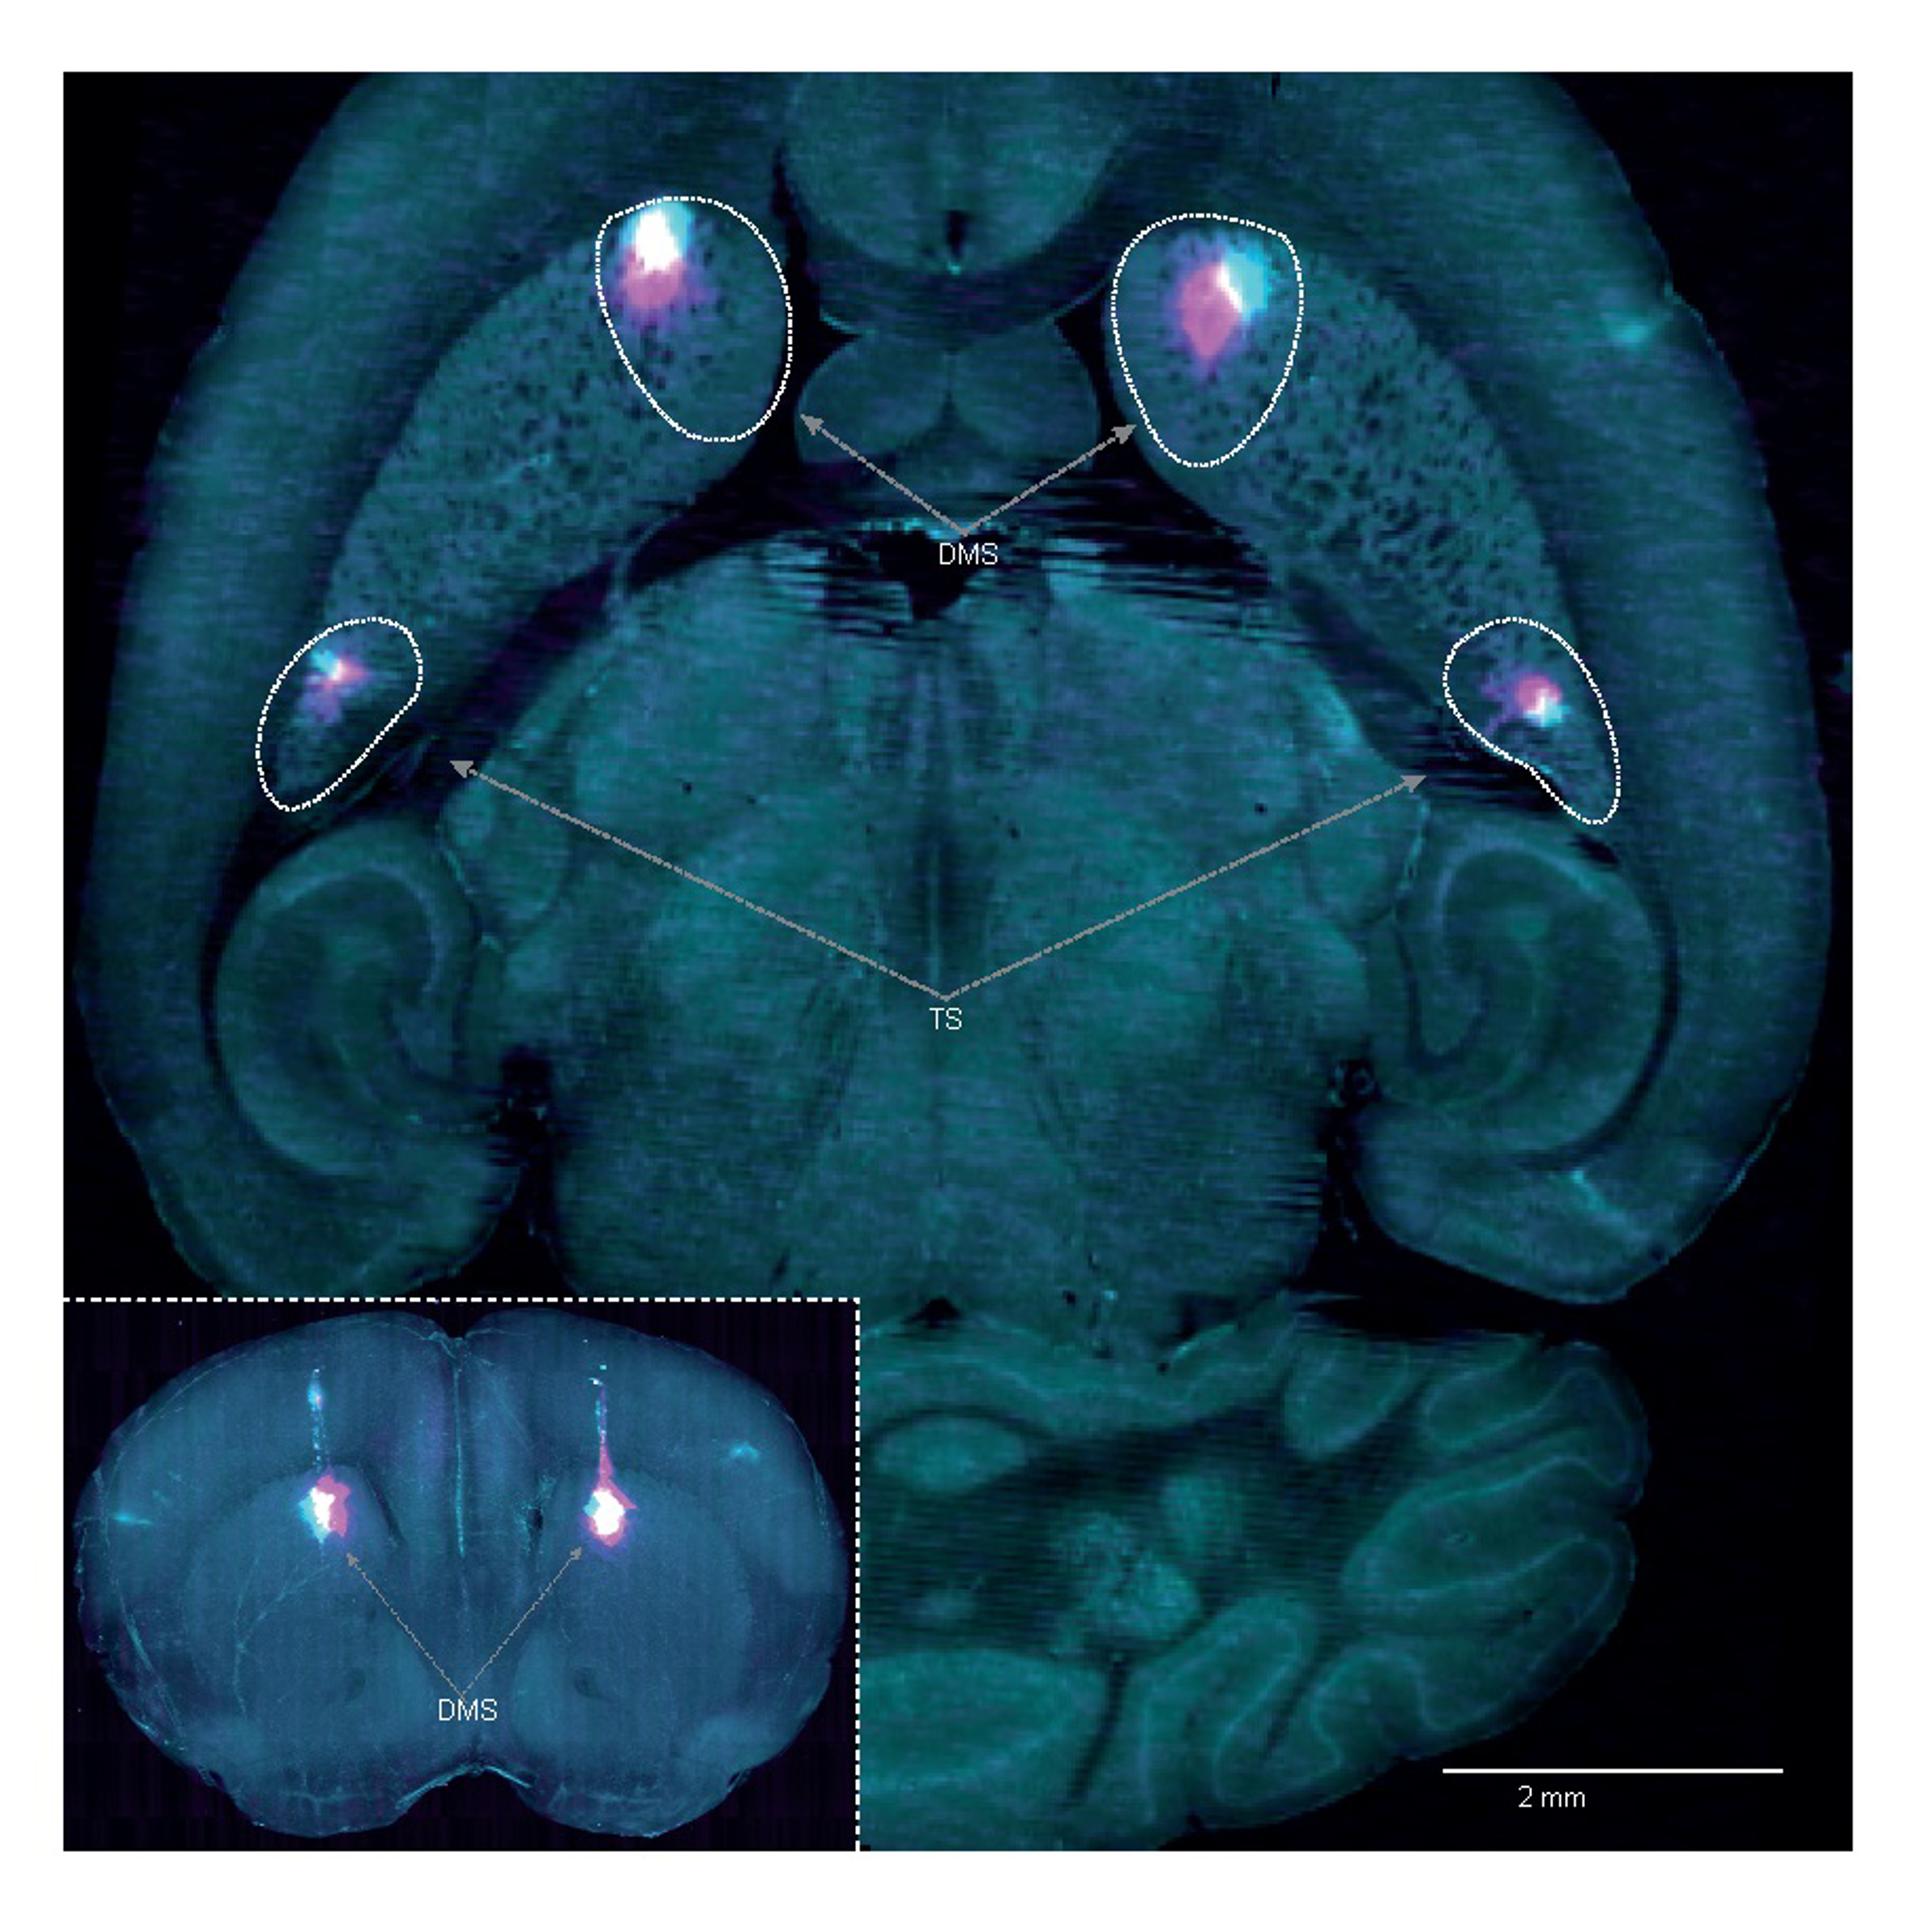

Los investigadores descubrieron una señal de dopamina (un neurotransmisor) en el cerebro que actúa como un tipo de señal didáctica diferente a la conocida hasta ahora.

En este nuevo estudio, los autores descubrieron que en paralelo a los errores de predicción de recompensa, hay una señal dopaminérgica adicional, denominada error de predicción de la acción (APE), que actualiza la frecuencia con que se realiza una acción.

Neuronas dopaminérgicas

Esta investigación también tiene implicaciones potenciales para el Parkinson, que se sabe que está causado por la muerte de neuronas dopaminérgicas del mesencéfalo, las relacionadas con el movimiento, que pueden ser responsables de la codificación del APE, lo que podría explicar por qué estos pacientes tienen dificultades para realizar tareas habituales como caminar, pero pueden realizar conductas más flexibles como patinar sobre hielo.